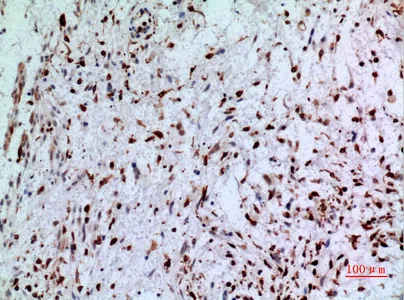

Cdk6 Rabbit Polyclonal Antibody

Cat: APRab08569